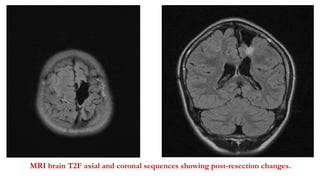

Surgery

• Resection of left frontal gliotic area.

• Post- resection ECoG did not show any spikes, fast activity.

• No new deficits were noted.

• HPE: reactive gliosis and localised inflammation.

MRI brain T2F axial and coronal sequences showing post-resection changes.